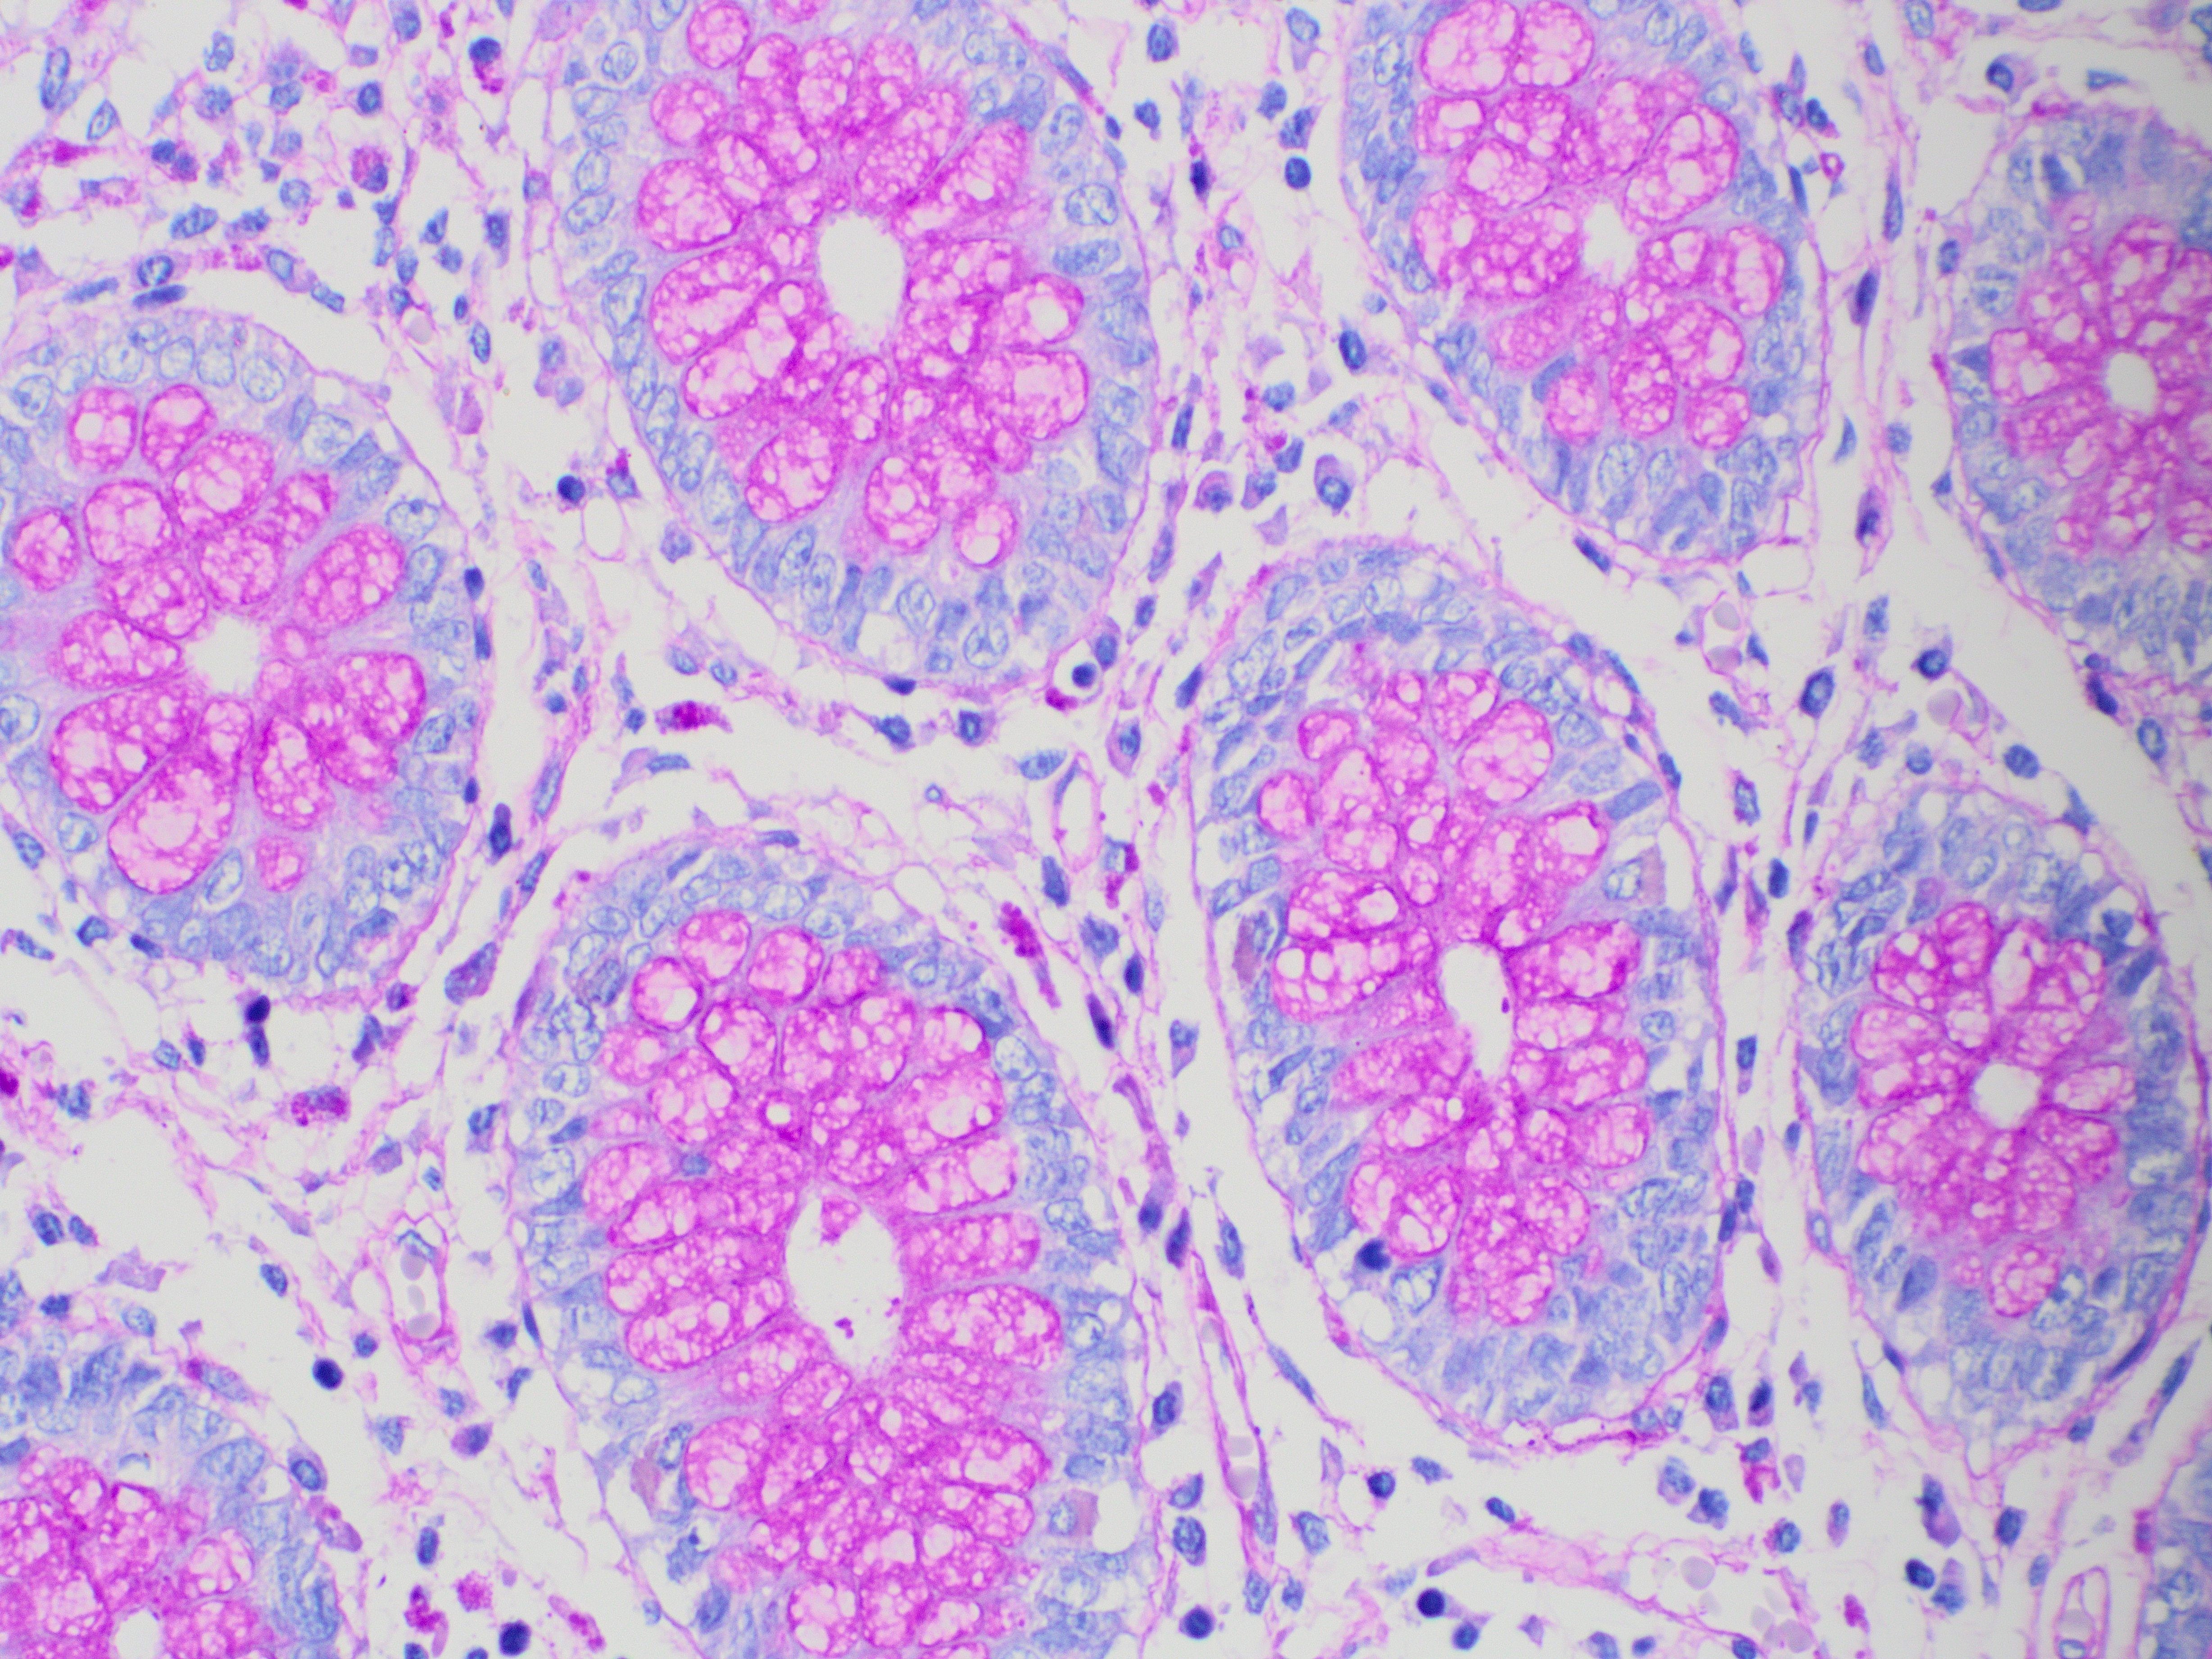

PAS-Schiff staining is widely used in histology and even in hematology with peripheral blood smears. This technique is used to identify polysaccharides, mucopolysaccharides, glycogen, and other substances containing glycol groups in biological tissues and cells.

Its mechanism is based on the glycol groups oxidation by periodic acid, a powerful oxidant that converts them into aldehydes. These react with Schiff’s reagent, where the fuchsin contained in the reagent binds to the aldehydes, forming an intense magenta color and revealing the presence of carbohydrates.